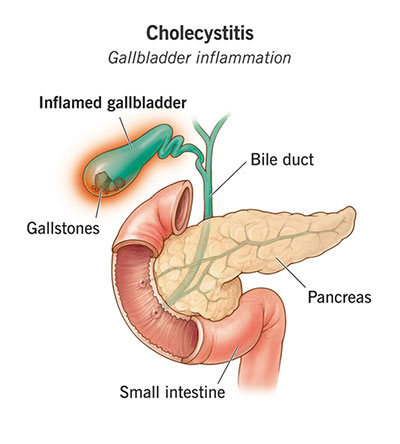

If the stone remains lodged for several hours, the gallbladder may become inflamed and infected, a condition called acute cholecystitis. This causes sharp pain, especially on the right side of the abdomen, and is often accompanied by fever. Acute cholecystitis typically requires hospitalization for intravenous antibiotics and removal of the gallbladder. In more severe cases, if a stone becomes deeply impacted, the gallbladder may become gangrenous, a life-threatening emergency that demands immediate surgical intervention.

Additionally, gallstones can migrate into the bile duct, potentially causing jaundice or blocking the pancreatic duct, which can lead to pancreatitis.